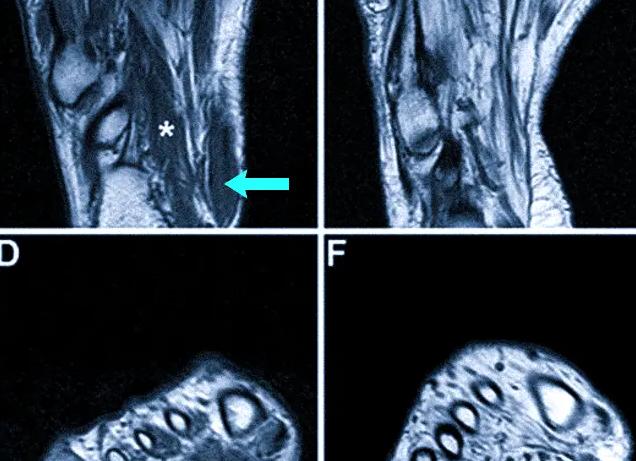

Томография тканей голени

МРТ мягких тканей голени осуществляют, используя контрастное вещество, так как этот отдел конечности особенно трудно поддается диагностике. Контраст вводится непосредственно в бедренную артерию и помогает воссоздать более четкое изображение проблемной области. Полученные снимки свидетельствуют о состоянии нервных волокон, мышц, связок, хрящевых структур, указывают на наличие в них воспалительных процессов. Проводят также и КТ костей голени.

При проведении МРТ сосудов нижних конечностей используют специальные контрастные препараты. Вещество вводят в бедренную артерию непосредственно перед началом процедуры сканирования. Данный метод помогает провести анализ состояния вен, артерий и лимфатических сосудов, улучшает видимость на снимке воспалений, метастазов, новообразований на ранней стадии. В качестве контраста используют парамагнитные препараты на основе гадолиния.

Для получения максимальной информации после обследования нижних конечностей врачи назначают магнитно-резонансную томографию с применением контраста. Обычно его используют при жалобах на болезненность, дискомфорт в ногах неясного происхождения. Такое обследование носит название ангиографии. Контраст вводится в бедренную артерию непосредственно перед сеансом МРТ.

Преимущество использования контрастного вещества заключается в том, что на снимках врач увидит всю сосудистую систему нижних конечностей. Есть возможность оценить скорость потока крови в артериях и венах, выявить начало нарушений в стенках сосудов, проверить состояние лимфоузлов ноги.

Контрастным веществом является гадолиний. Он быстро растворяется, хорошо переносится, накапливается в повреждённых участках сосудистой системы, поэтому на снимках они выглядят ярче. Контрастное вещество не остаётся в организме, через некоторое время оно выводится почками.

Пациент размещается на кушетке. Для обеспечения неподвижности, исключения случайных движений, конечности пристегнут мягкими ремнями. При необходимости вводится контрастное вещество в бедренную артерию, кушетка плавно въезжает в тоннель томографа. При обследовании ног пациент может частично находиться в аппарате. Например, при МРТ голени или ступни в аппарат помещают только ноги.